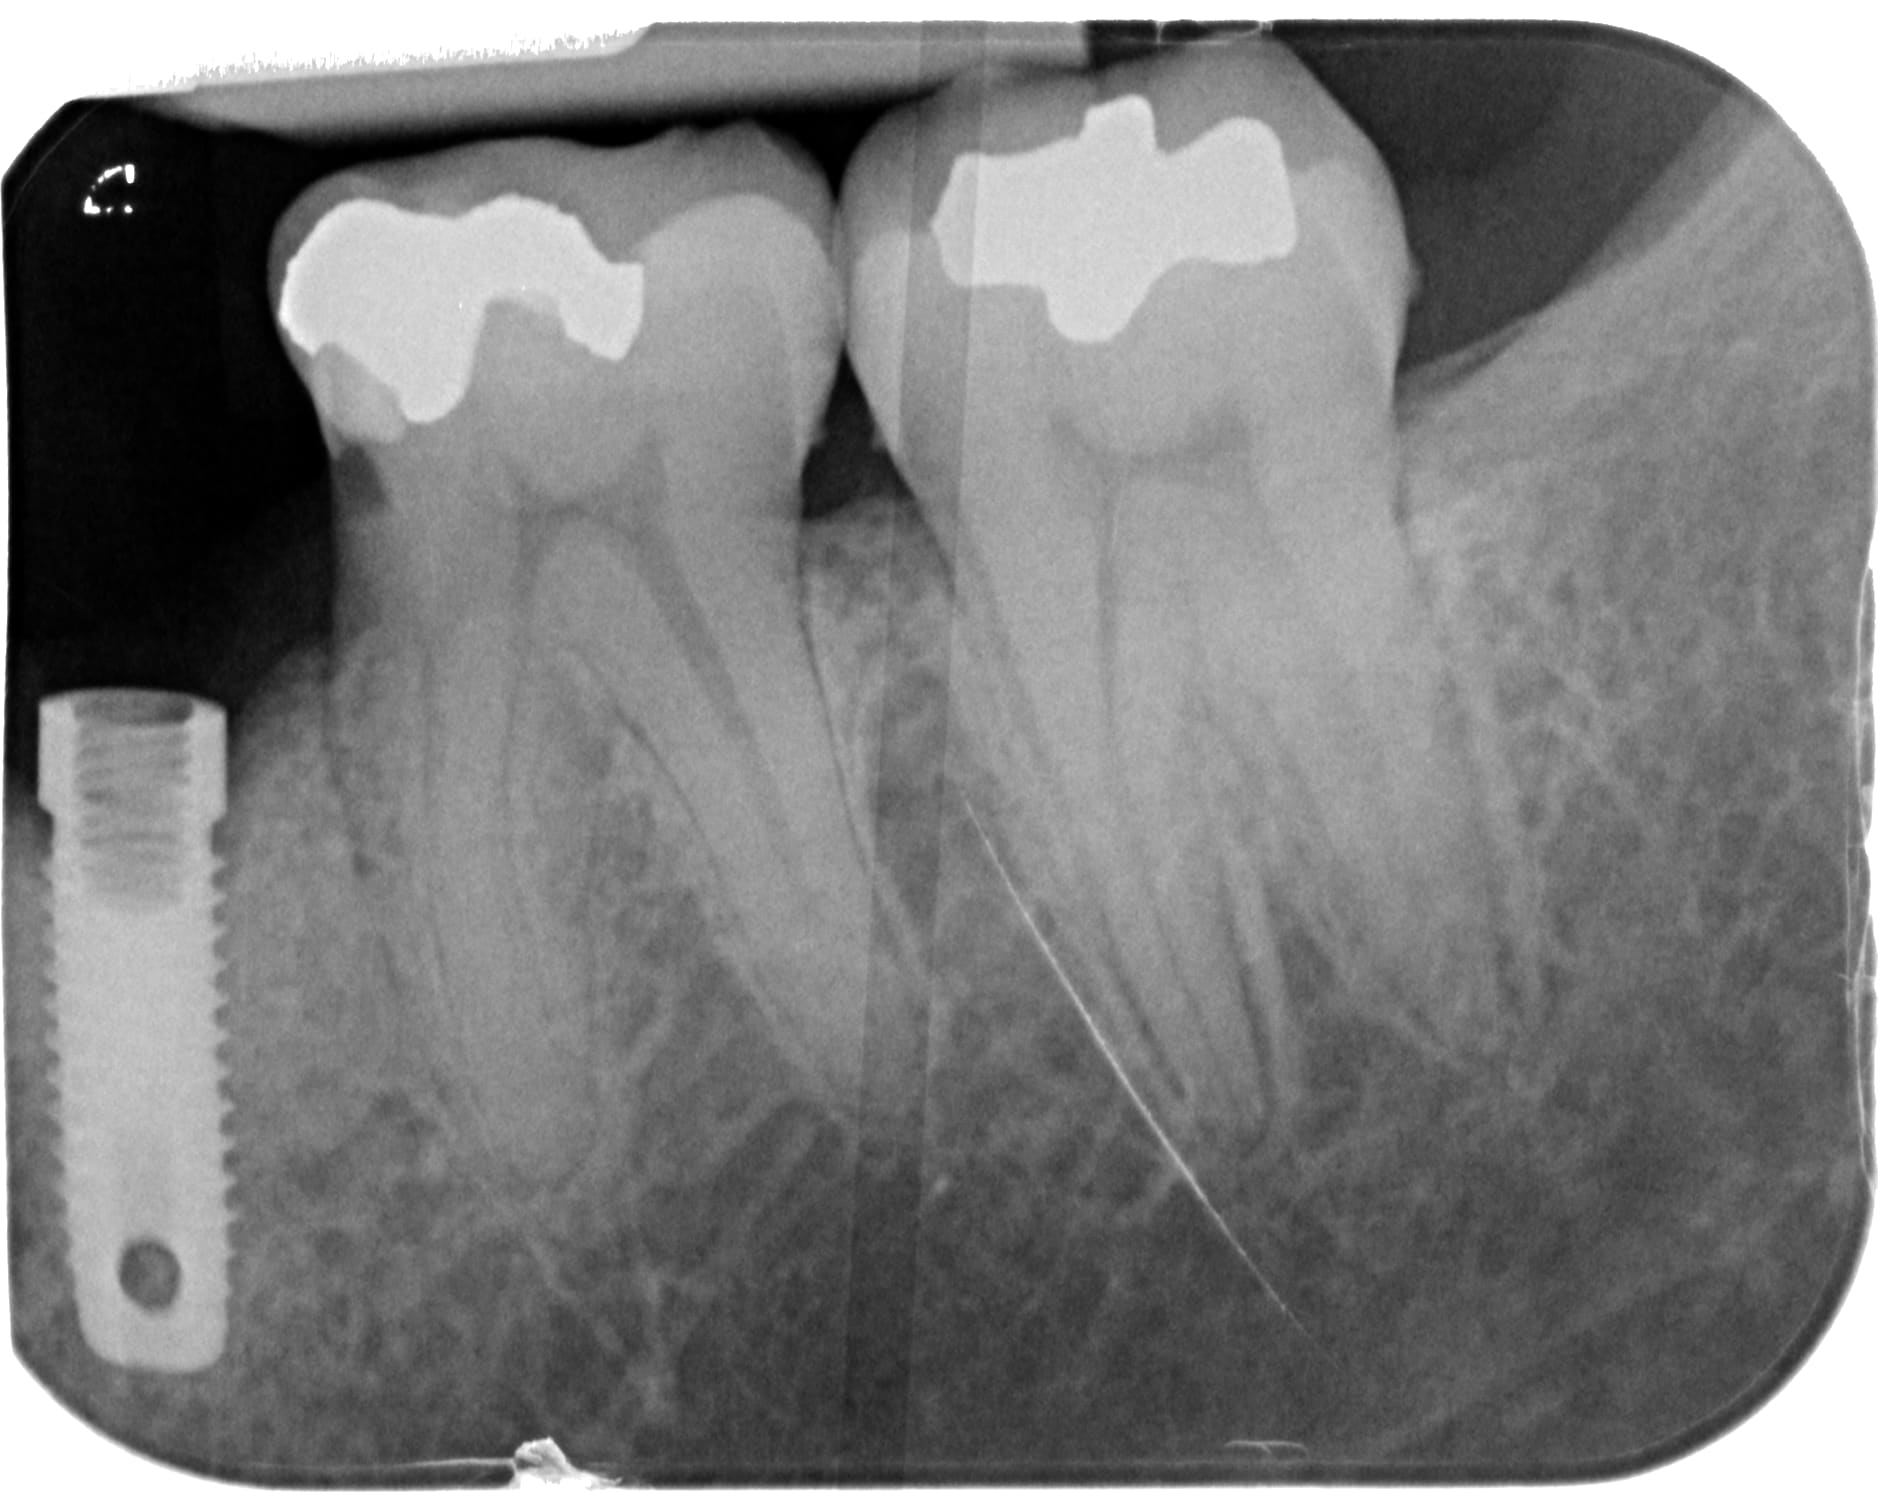

Bonjour à tous, avez vous une idée de la marque d'implant pour eux à la mandibule?

https://www.spotimplant.com/fr/implants-dentaire/steri-oss/steri-oss-original-non-hex

Autant te dire que tu peux chercher longtemps pour trouver des composants….c’est mort….

ha merde... aucune compatibilité avec un autre systeme?